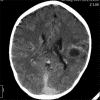

We present two cases of polycythemia secondary to a congenital cardiac anomaly presenting with acute neurological complications showing hyperdense venous sinuses and cerebral vasculature in association with cerebral abscess.